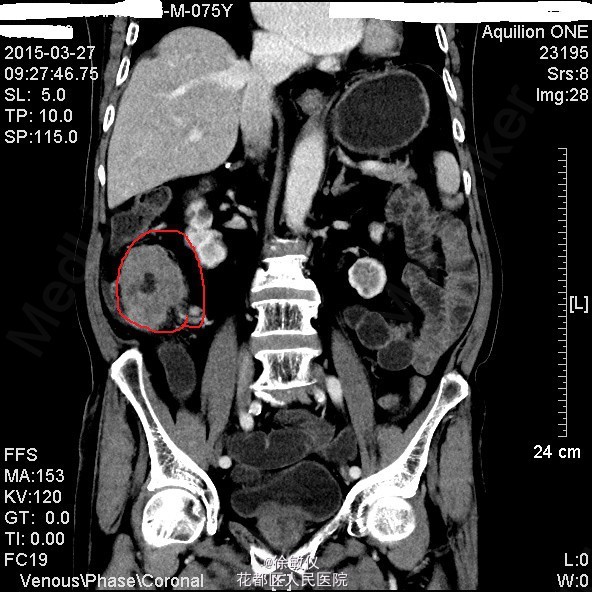

查体:生命体征平稳,贫血面容。腹软,全腹无压痛、反跳痛,右中腹可触及一大小约4*5cm包块,边界清晰,质稍硬。肝脾肋下未触及。 辅查:HGB 82g/L;CA19-9 625.97U/ml;CA-125 24.9U/ml;大便常规示:粪血红蛋白试验阳性。 全腹CT平扫+增强示:1、结肠肝曲及升结肠癌,浸润肠壁全层,周围多发淋巴结转移;2、直肠多发小息肉;直肠下段静脉曲张。